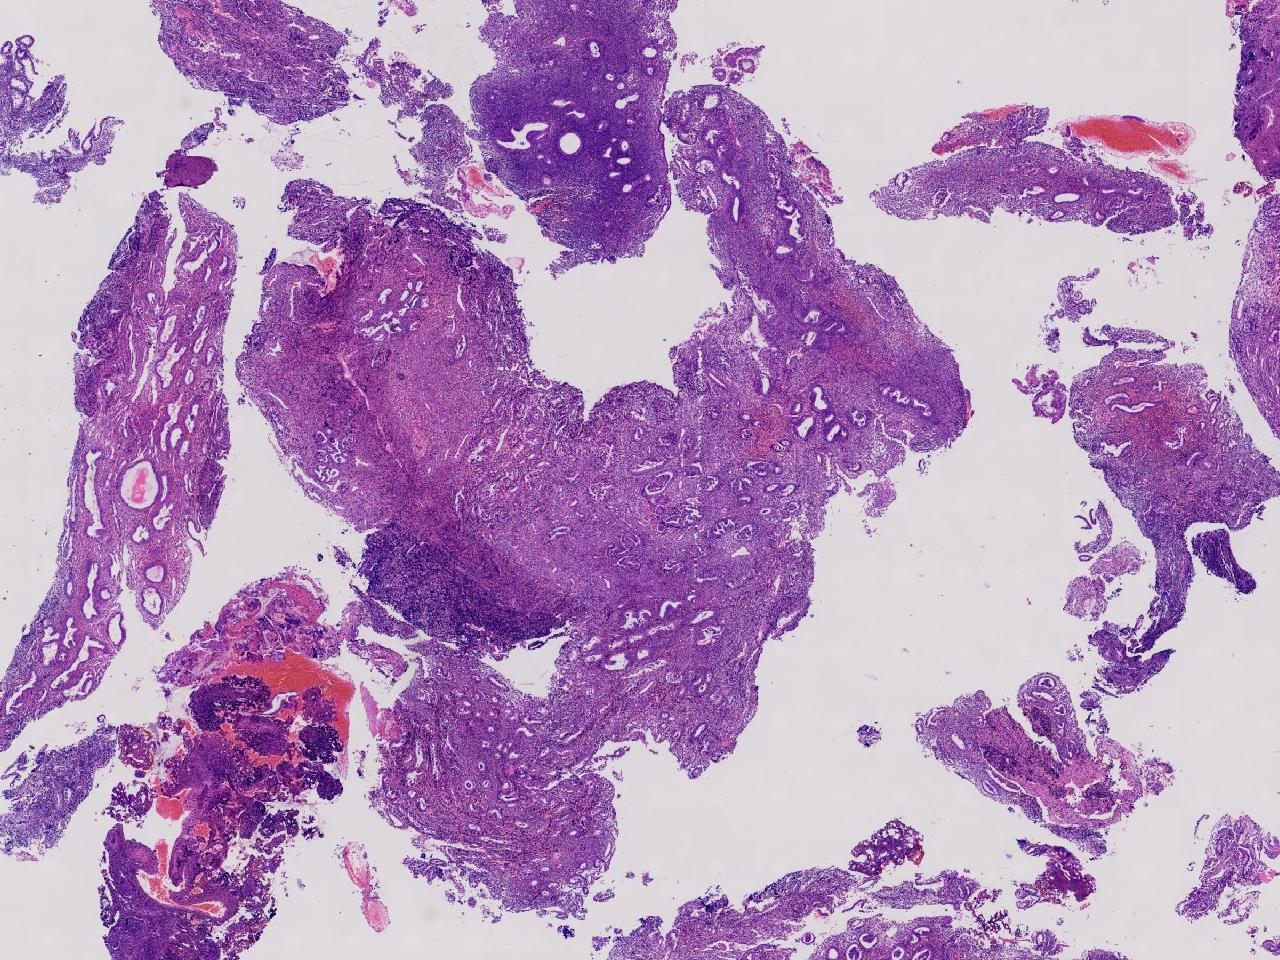

性别

女

年龄

55岁

女,55岁,月经紊乱4年,彩超示:子宫内膜增厚(内膜厚15.7mm),末次月经:2025年7月27日。

标本名称

宫腔镜下子宫内膜活检

大体所见

灰粉色不整形软组织多块,1.5X0.8X0.6厘米。

考虑:子宫内膜增生伴子宫内膜炎

子宫内膜增生紊乱,内膜息肉样结构